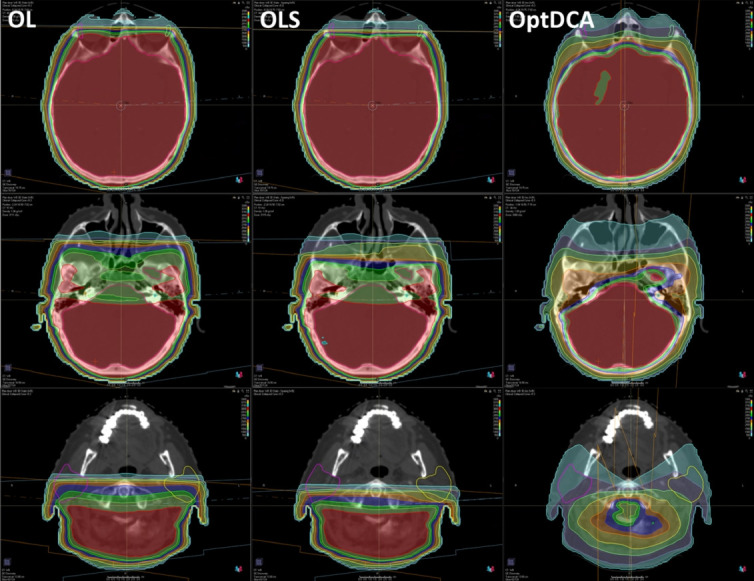

Purpose: Our purpose was to compare four whole brain radiotherapy (WBRT) delivery types: opposed lateral (OL) 3-dimensional-conformal radiotherapy (3D-CRT), a novel opposed lateral sparing (OLS) 3D-CRT technique, 3D optimized dynamic conformal arcs (optDCA), and hippocampal-avoidant WBRT (HA-WBRT).

Materials and methods: Ten patients previously undergoing HA-WBRT were retrospectively planned using OL, OLS, and optDCA techniques. OLS technique involved multi-leaf collimator (MLC) modifications to protect the lacrimal and parotid glands. OptDCA was inverse-planned 3D-CRT with dynamic conformal arcs. A dosimetric, cost, and resource utilization comparison was performed.

Results: Planning target volume coverage to prescription dose between 3D planning techniques was not significantly different between OL and OLS techniques (96.8% vs. 96.6%, p = 0.855), or between OL, OLS, and optDCA (95.0%) techniques (p = 0.079). There was no difference in the heterogeneity index between 3D plans (p = 0.482); all were less heterogeneous than HA-WBRT (p < 0.001). OptDCA was more conformal than OL and OLS, and similar in conformity to HA-WBRT. OLS achieved significant sparing of lacrimal and parotid glands over OL. There were significant step-function reductions in organ at risk (OAR) dose when comparing OL to OLS to optDCA to HA-WBRT plans. HA-WBRT was 57% more expensive than OL and OLS technique. HA-WBRT took approximately six times longer to plan.

Conclusion: We showed adequate and equivalent target coverage using OL, OLS, and optDCA techniques. Lacrimal and parotid dosages can be greatly reduced with the implementation of minor MLC adjustments. OptDCA therapy represented further improvement of these modifications, and was comparable to HA-WBRT in terms of OAR dose, while being about two-thirds the cost and more efficient to plan.